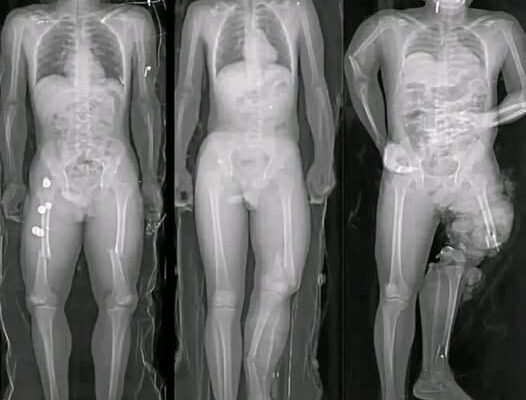

Medical research has identified a small number of myocarditis cases—an inflammation of the heart muscle—following certain mRNA vaccines, particularly among adolescent and young adult males. However, context is critical. These cases are rare, typically mild, and most individuals recover fully with minimal treatment.

Multiple peer-reviewed studies show that the risk of myocarditis from COVID infection itself is significantly higher than the risk associated with vaccination. COVID-19 as a disease has been linked to more severe cardiac complications, including inflammation, blood clots, and long-term heart damage.